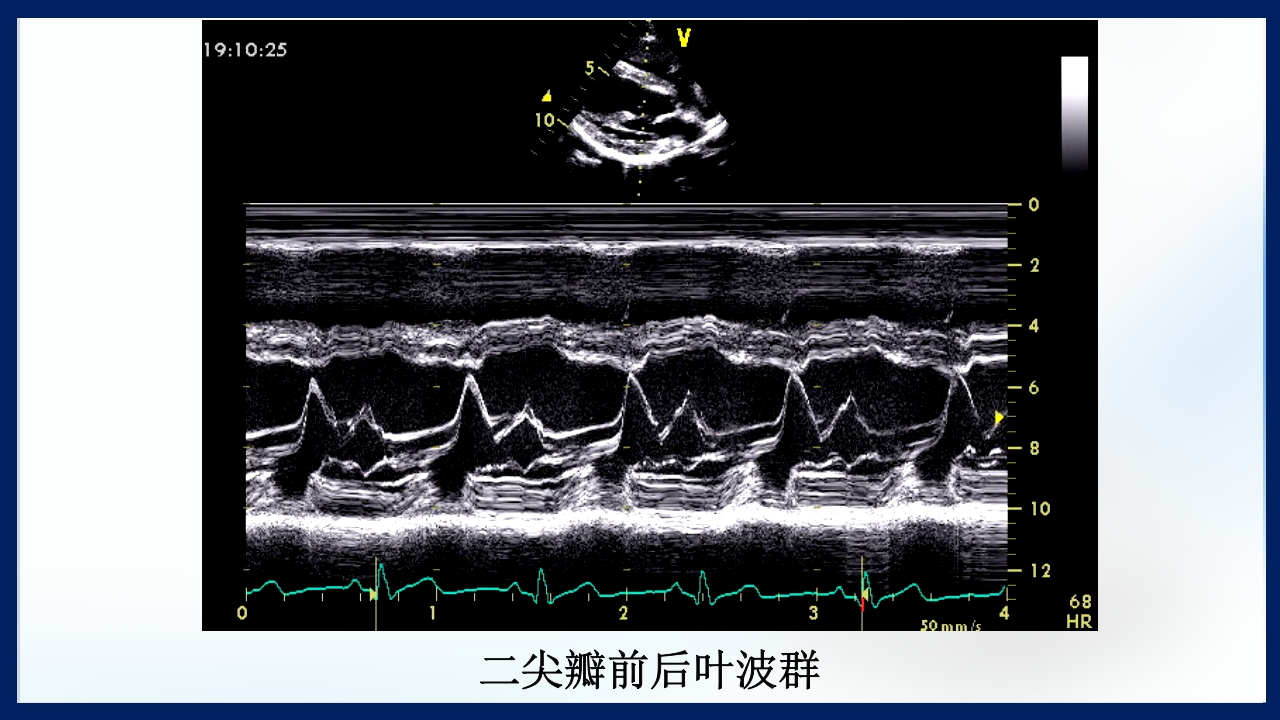

心 脏 瓣膜 医师:XXX 日期:20XX.XX.XX 讲授目的和要求 1 掌握二尖瓣和主动脉瓣膜病变的病理生理、临床表现及诊断方法。 熟悉二尖瓣和主动脉瓣膜病变的病因、鉴别诊断、并发症、治疗原则及 2 手术适应证。 3 了解瓣膜病的检查方法及治疗新进展。 心脏瓣膜病 是由于炎症、粘液样变性、退行性改变等原 因引起的单个或多个瓣膜结构的功能或结构异常,导致 瓣口狭窄及(或)关闭不全。二尖瓣最常受累,其次为 主动脉瓣。 (Rheumatic Heart Disease)简称风心病, 是风湿性炎症过程所致瓣膜损害,主要累及40岁以下人 群。 瓣膜粘液样变性和老年瓣膜钙化所致瓣膜病日渐增多。 3 瓣膜病分类 按病因分类: 风湿性、老年退行性、先天性、相对性 按受累部位和类型分: 二尖瓣狭窄、二尖瓣关闭...